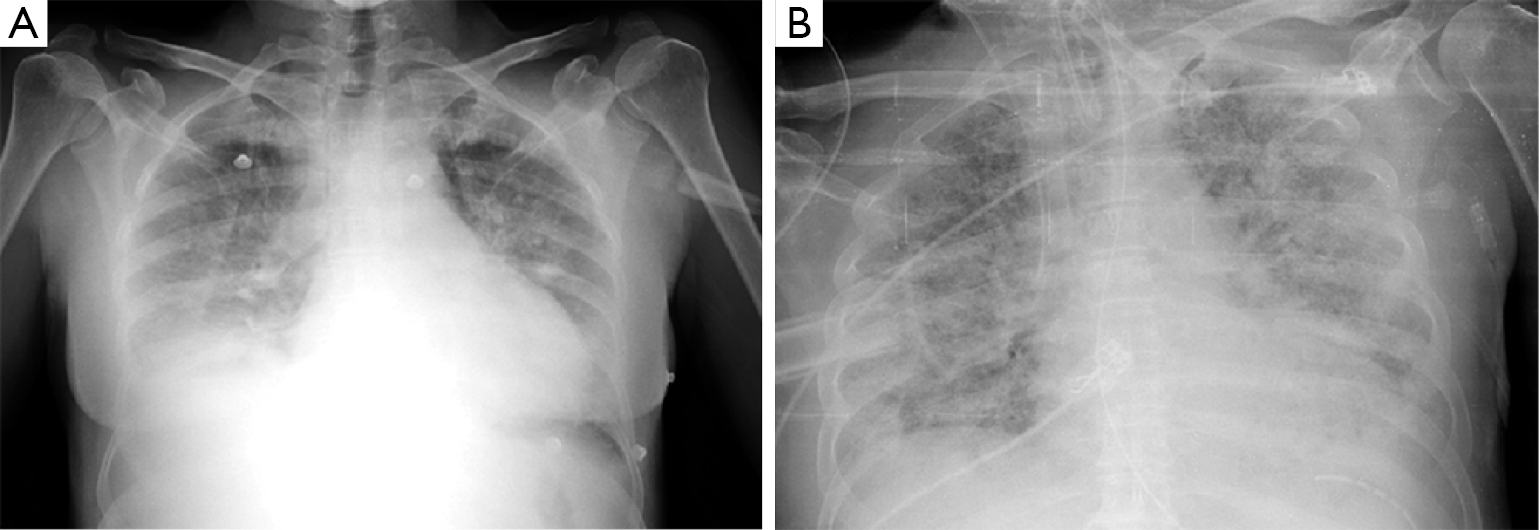

Acute respiratory distress syndrome (ards) & covid 19 treatment. Here a cxr with a reticular pattern at the lung bases. Acute respiratory distress syndrome (ards) is a form of acute lung injury and occurs as a result of a severe pulmonary injury that causes alveolar damage heterogeneously throughout the lung.

This pattern was first attributed to chronic congestive heart failure, but persisted on.